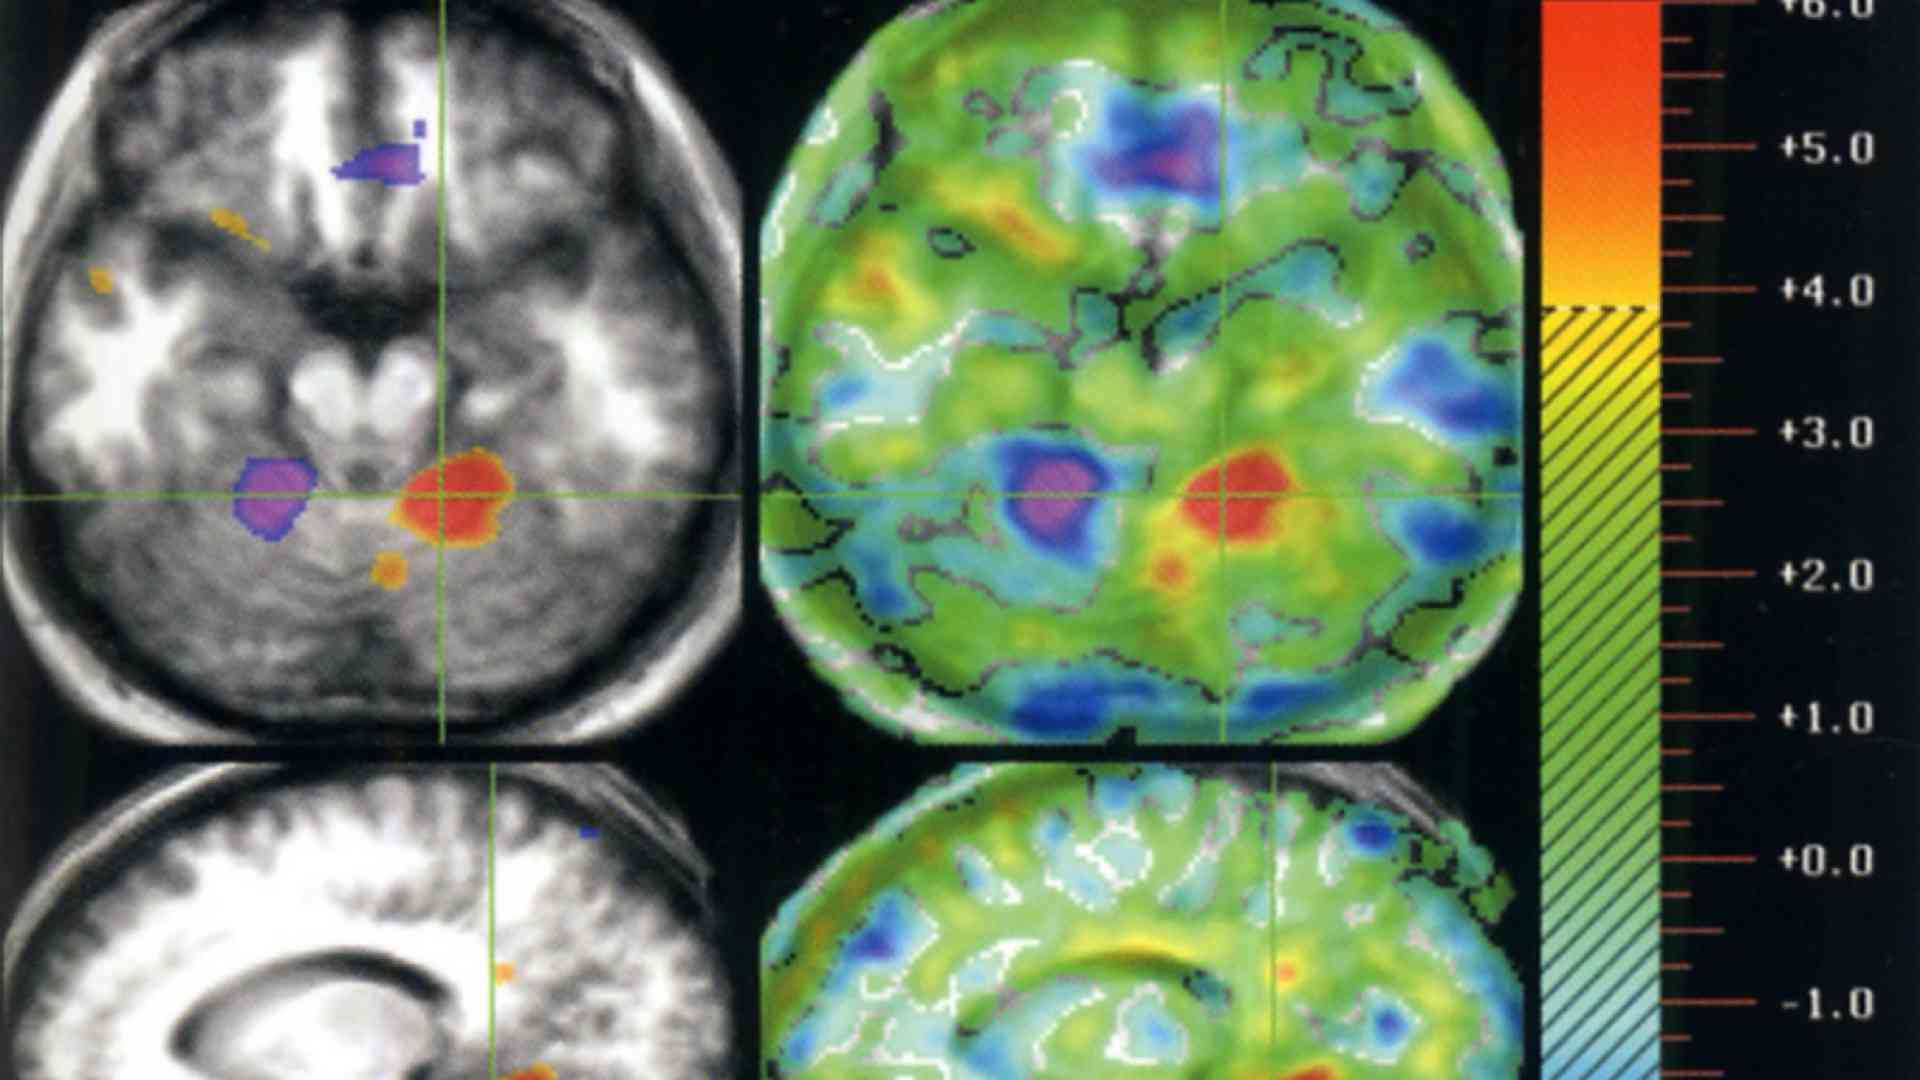

Dopo un ciclo di stimolazioni l'uomo è uscito dallo stato vegetativo entrando in uno stato minimo di coscienza, con capacità di muovere occhi e testa a comando, seguire un oggetto con lo sguardo, rispondere a stimoli esterni. Il suo elettroencefalogramma ha cominciato a registrare segni di attività neurale ormai assenti da 15 anni; con la PET, inoltre, gli esperti hanno visto la comparsa di nuove connessioni nervose, segno che il cervello resta plastico anche dopo anni di stato vegetativo.